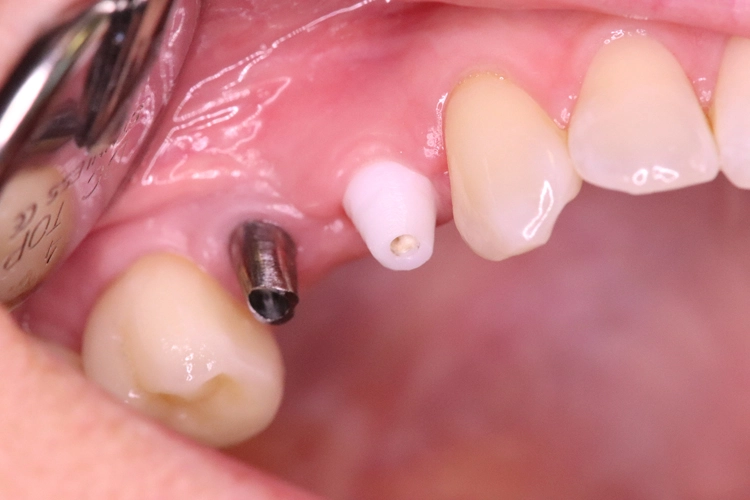

Nach der ersten klinischen Befundaufnahme und Fotodokumentation der Ausgangssituation (Abb. 1) wurde zur Ergänzung des klinischen Befundes eine Einzelzahnaufnahme erstellt (Abb. 2). Vom Oberkiefer wurde eine Abformung genommen, um eine Tiefziehschiene herzustellen. Diese wird direkt am OP-Tag genutzt, um eine provisorische Krone herzustellen.

Aufgrund der traumatischen Extraktion des ankylosierten Zahnes, die zu einer Osteotomie wurde (Abb. 3), fehlten die vestibuläre und palatinale Lamelle (Röntgenkontrollbild während der Osteotomie, Wurzelrest noch vorhanden Abb. 4). Dieser Wurzelrest wurde entfernt. Bei dem geringen Restknochenvolumen war eine Sofortimplantation nicht mehr indiziert.

Die Implantate wurden provisorisch versorgt (Abb. 17). Kontrolle nach einer Woche mit Nahtentfernung (Abb. 18). Präparation und Abformung nach zwei Wochen.